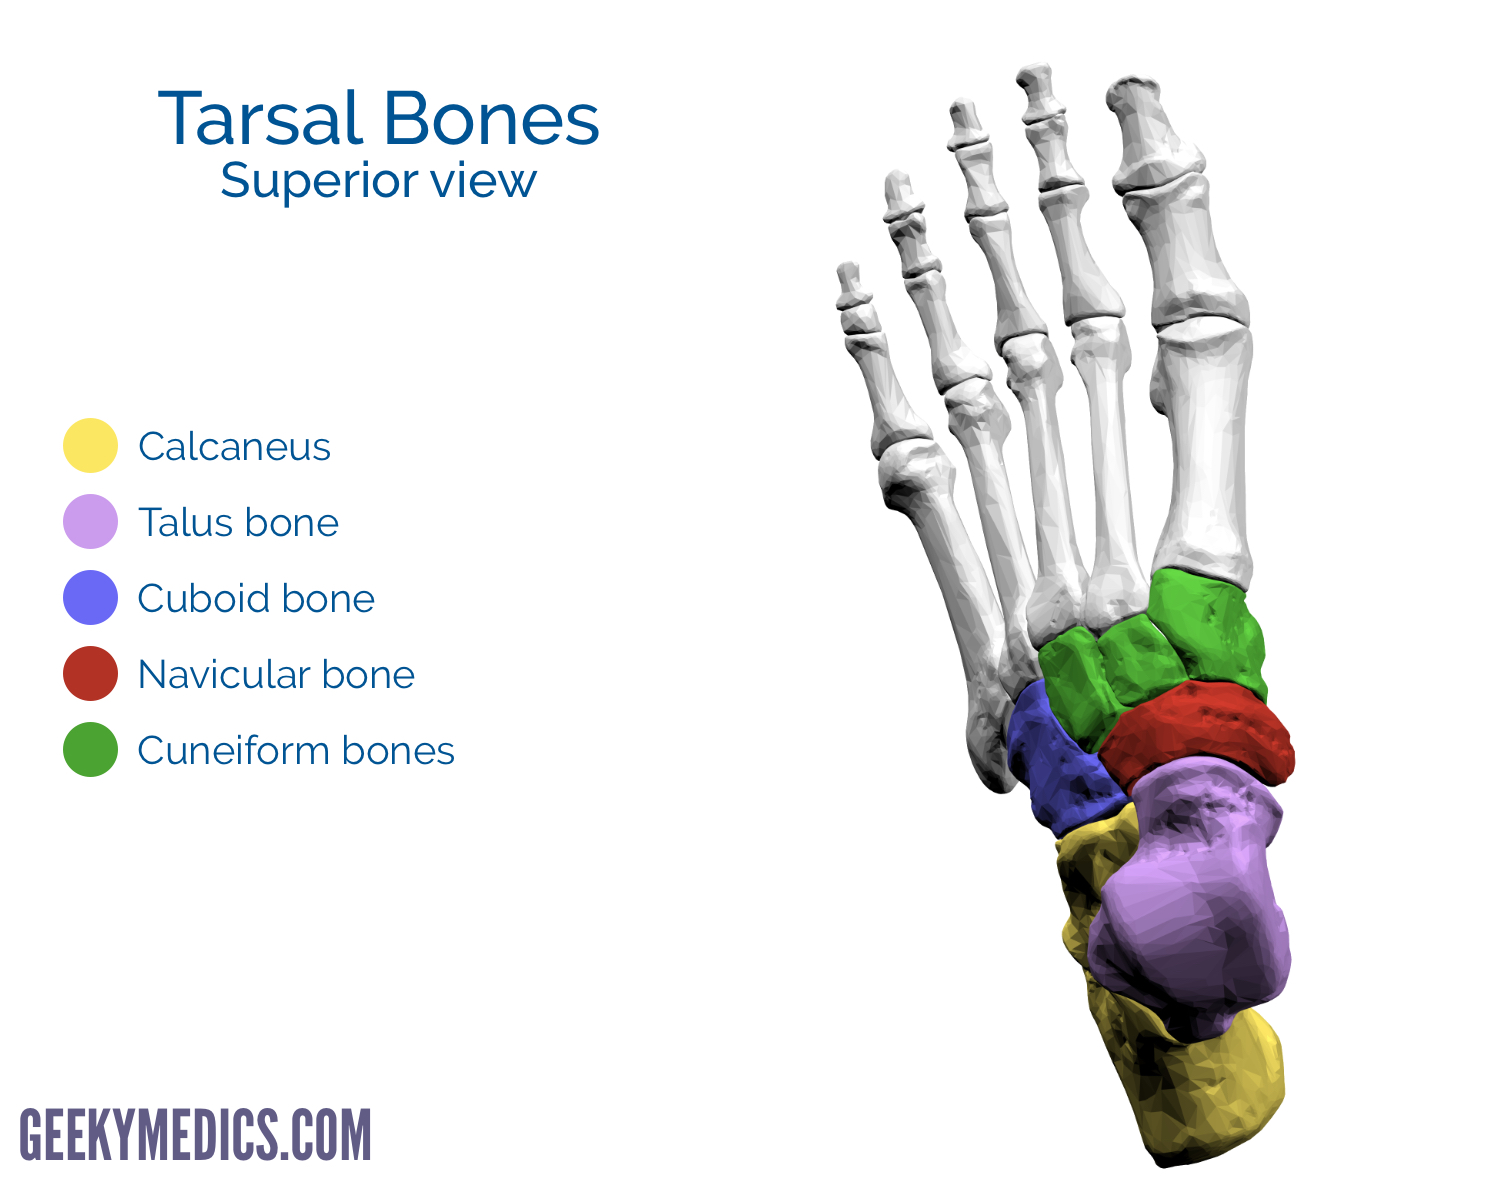

tarsals: 7

Explain the size and location of the 3 cuneiforms

1st: medial (largest)

2nd: intermediate (smallest)

3rd: lateral

The navicular is located on the ___ side of the foot and articulates distally with ___

medial; the cuneiforms

The cuboid is located on the ___ side of the foot and articulates distally with ___

lateral; MT 4 and 5